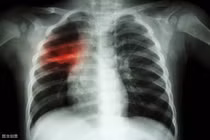

Tranh thủ kỳ nghỉ đông, Lý Thiến Sơn đến bệnh viện địa phương khám. Kết quả ban đầu không mấy khả quan nên bác sĩ chỉ định thực hiện thêm nhiều xét nghiệm khác. Kết quả cho thấy, Lý Thiến Sơn mắc ung thư phổi. (Ảnh minh họa)